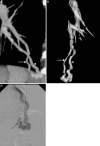

This pictorial review is based on our experience of the follow-up of 120 patients at our multidisciplinary center for hereditary hemorrhagic telangiectasia (HHT). Rendu-Osler-Weber disease or HHT is a multiorgan autosomal dominant disorder with high penetrance, characterized by epistaxis, mucocutaneous telangiectasis, and visceral arteriovenous malformations (AVMs). The research on gene mutations is fundamental and family screening by clinical examination, chest X-ray, research of pulmonary shunting, and abdominal color Doppler sonography is absolutely necessary. The angioarchitecture of pulmonary AVMs can be studied by unenhanced multidetector computed tomography; however, all other explorations of liver, digestive bowels, or brain require administration of contrast media. Magnetic resonance angiography is helpful for central nervous system screening, in particular for the spinal cord, but also for pulmonary, hepatic, and pelvic AVMs. Knowledge of the multiorgan involvement of HHT, mechanism of complications, and radiologic findings is fundamental for the correct management of these patients.